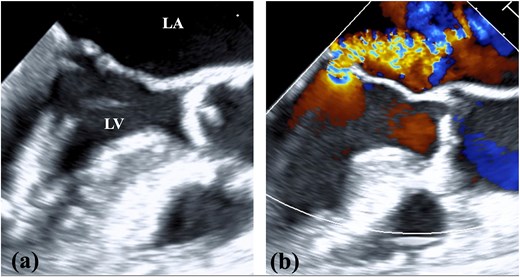

A 78-year-old woman with severe mitral regurgitation (MR), tricuspid regurgitation, and atrial fibrillation was admitted with worsening heart failure. She had hypertension, but no known CHD. She was 138 cm tall, weighing 34.6 kg, with a body mass index of 18.3 kg/m2. Her vital signs were normal. The N-terminal fragment of pro B-type natriuretic peptide was elevated at 2577 pg/mL. Chest radiography revealed cardiac enlargement and bilateral pulmonary edema. Transesophageal echocardiography (TEE) revealed shortening of the anterior and posterior leaflets of the mitral valve, with thickening of the commissure, indicating severe MR (Fig. 1 and Video 1). The tricuspid annulus diameter increased to 29.4 mm. No congenital heart diseases were detected. Contrast-enhanced computed tomography (CT) revealed that the left innominate vein coursed posterior to the ascending aorta, the so-called ALBCV, and joined the superior vena cava (SVC) 3 cm from the right atrium (Fig. 2 and Video 2). Venography of the left upper limb confirmed the ALBCV (Fig. 3 and Video 3). No communication existed between the ALBCV and the coronary sinus.

TEE findings. (a) Shortening of the anterior and posterior leaflets of the mitral valve was noted with thickening of the commissure. (b) Both valve leaflets were shortened and the coaptation zone was stiff, resulting in severe MR. LA, left atrium; LV, left ventricle.